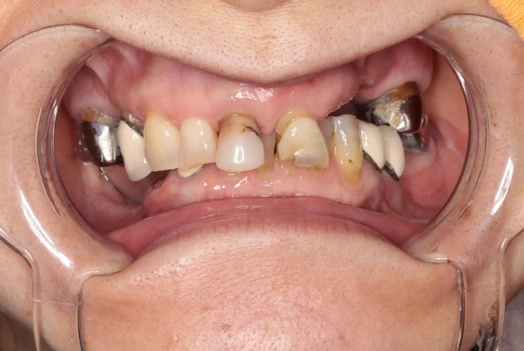

オールオン4 症例①

オールオン4 症例

大きな手術のイメージがあって、怖い

持病があり、手術が心配

素早く終わらせてほしい

治療例

オールオン4 症例②

オールオン4 症例③

費用例

総額 4,884,000円(税込)

年齢

60代女性

主訴

噛めない

治療期間

1年

施術(治療)内容

オールオン4と前歯2本のセラミック治療

リスク・副作用

外科的侵襲がある、費用が高い

麻酔費用

33,000円×3回=99,000円

治療費用

4,884,000円(税込)

4,785,000円(税込)